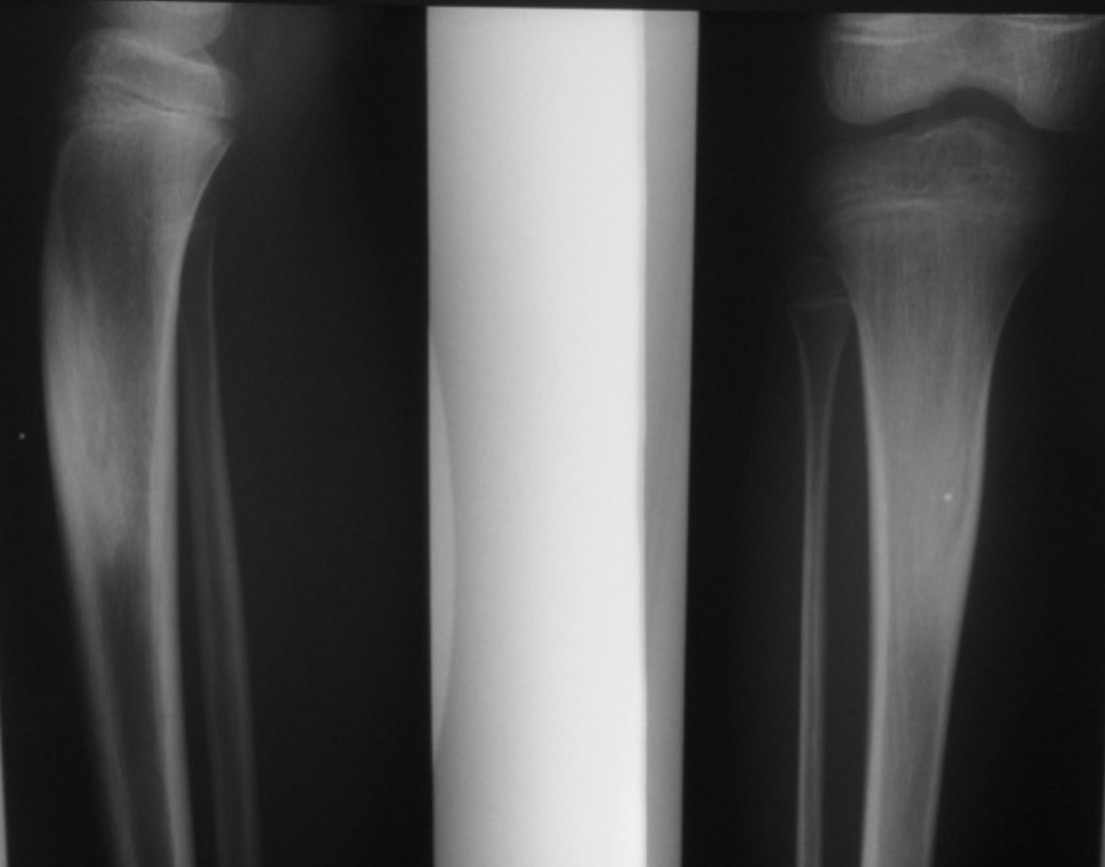

X-ray

Sclerotic bone

Osteoid osteoma tibia

Osteoid osteoma femur